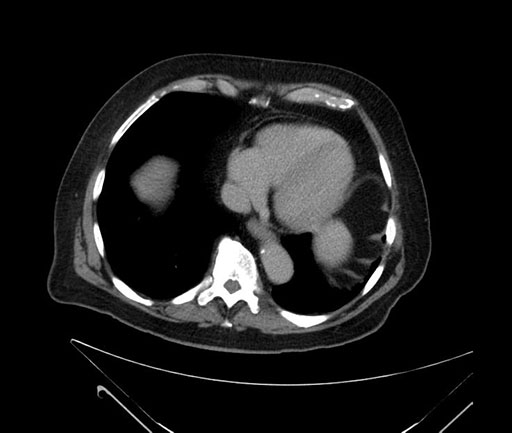

Imaging Analysis

Look through the patient's CT scan to identify any areas of concern for the necessary procedure.

Based on your CT findings, which issue(s) would give reason for "planned slowing down moment(s)" in this case?